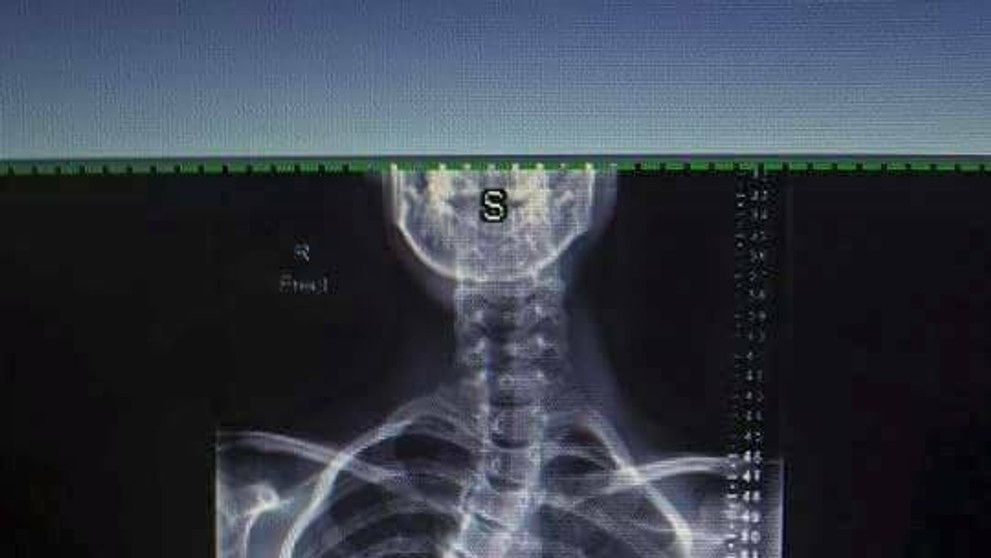

Sam Hansen a jej chrbtica predtým a teraz.

Mladá Novozélanďanka Sam Hansen má vzácnu chorobu. Ide o idiopatickú skoliózu. Chrbticu mala vykrivenú o 55 stupňov. Prvýkrát si to všimla, keď mala dvanásť rokov a chcela sa zohnúť pre niečo na zemi. Rodičia si všimli, že jej zvláštne trčia rebrá. Začala nosiť veľké a rozťahané veci, aby to zakryla.

Sam podstúpila operáciu, po ktorej má v tele sedemnásť skrutiek a dve železné tyče. Ako píše mirror.co.uk, narástla po nej o desať centimetrov. Chrbtica sa jej o dosť narovnala, teraz ju má vykrivenú len o 20 stupňov, čo je už prijateľné. Jej zdravotný stav sa zlepšuje a už začala aj športovať.